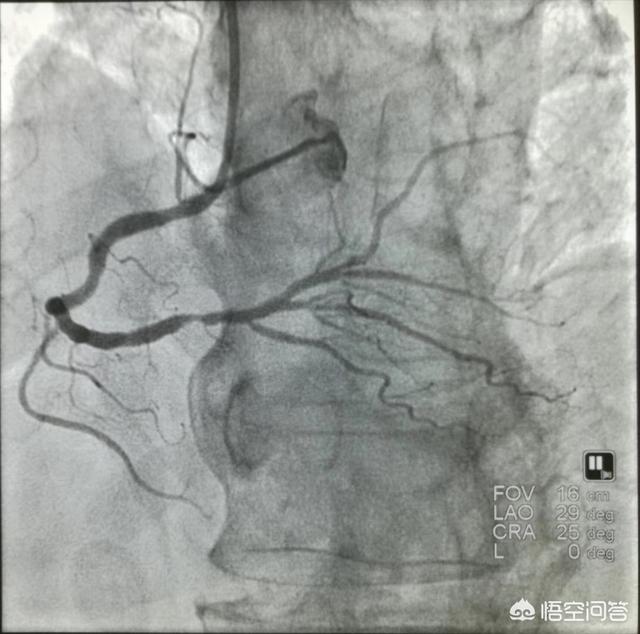

冠動脈CTは血管が狭くなっているかどうか、どの程度狭くなっているかを見ることができ、冠動脈疾患の診断を確定することができる。典型的な冠動脈疾患の患者に対しては、さらに冠動脈造影を行い、一方では診断を確定し、他方ではさらなる治療を行うことができる。

診断という点では、冠動脈疾患のゴールドスタンダードは依然として冠動脈造影検査である。安全ではあるが、侵襲的な検査であることに変わりはない。そのため、医師は十分な裏付けがある場合にのみ、この検査のための入院を勧める。この検査には、患者の病歴、症状、身体所見、過去の病歴、家族歴、心電図、胸部X線、心筋酵素、心エコー、プレート運動負荷試験などが含まれる。現在では,入院することなく外来で冠動脈CTAを受けられる患者もいる。 この検査は冠動脈疾患に対してより直接的に反応するものであるが,冠動脈造影検査と比較するとまだ多くの欠点があり(例えば,粥腫性プラークのアーチファクトは偽陽性を招き,血流や血管の動的な変化を同定することはできないなど),予備的なスクリーニング検査としてしか使用できない。

①明確な診断冠動脈性心疾患の診断は、現在の医療レベルでは、次のような方法で難しいことではない。冠動脈造影冠動脈疾患の確定診断ができる。冠動脈に直接カテーテルを通し、造影剤を出して冠動脈を画像化することで、閉塞の場所や程度が明確になり、その後の治療の根拠となります。これが冠動脈疾患の最も一般的な治療法である理由です。冠動脈疾患診断の "ゴールドスタンダード"。。

冠動脈疾患の診断は系統的な問題である。 第一に、冠動脈疾患の診断は典型的な冠動脈疾患の症状の有無に依存している。 患者が活動後に胸が締め付けられるような感じや息切れがあれば、冠動脈疾患であるかどうかを検討する必要がある。 しかし、冠動脈疾患のすべての患者に典型的な症状があるわけではなく、冠動脈疾患の患者の中には非典型的な症状があったり、まったく症状がなかったりする場合もあり、冠動脈疾患と診断するためにはさらに検査を行う必要がある。第二に、冠動脈疾患の診断は冠動脈の関連検査に依存し、冠動脈検査には主に冠動脈CT、冠動脈造影などの画像データが含まれる。もちろん、冠状動脈疾患の確定診断が必要な場合は、心臓超音波検査、血液検査、磁気共鳴検査などの関連検査も冠状動脈疾患の診断確定に必要である。